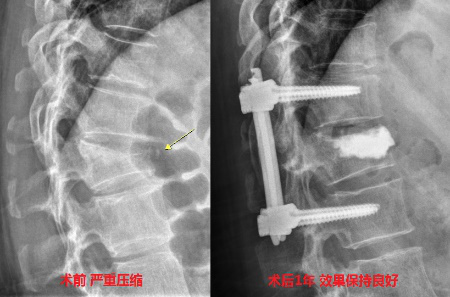

因为此类患者群体普遍具有年龄大、基础病多、骨强度显著下降、伤椎椎体压缩严重、骨折局部后凸畸形,特别是椎体后壁破损不完整等特点,使得手术治疗过程中极易产生问题。

为最大程度减少手术创伤,同时减轻患者身心和经济负担,解决医护人员在手术中射线辐射问题,提高手术精准度,医院骨四科(脊柱外科)于2019年引入“天玑”骨科机器人。骨科机器人辅助技术可以在手术中进行辅助经皮椎弓根螺钉固定联合伤椎PKP技术,精准治疗椎体爆裂骨折。

自2019年以来,医院骨四科(脊柱外科)积累了大量机器人手术经验,通过采用“骨科机器人辅助技术”结合团队专家优势,充分发挥骨科机器人的自动导航定位优势,不仅极大减轻了患者创伤,还轻松解决了这一骨科临床难题,为广大椎体骨折患者带来了福音。